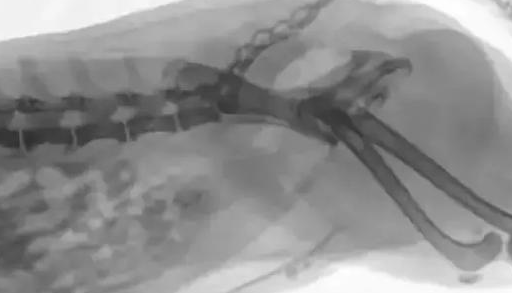

原因7、尿路堵塞

UTI’s、膀胱结石和犬胰腺炎

可损害整个肾脏系统

尿液积压压力会对肾脏产生后续作用

从而引起炎症

如果持续时间过久

将形成不可逆转的损害